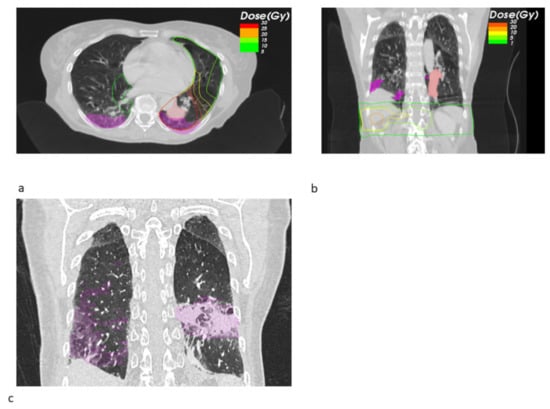

Figure 3. Sagittal radiotherapy (RT) planning CT slices showing the sum EQD2 isodoses and pneumonitis contours (magenta) for a SBRT+ ICB case (a). The same patient received simultaneous contralateral hypofractionated mediastinal RT with original isodoses revealing a relevant lung dose (b). Exemplary sagittal slice from the follow-up CT showing the bilateral pneumonitis and its contours (magenta) (c).

Looking at the dosimetric results in more detail, we observed a trend towards a decreased fraction of the pneumonitis volume receiving a high dose of EQD2 > 20 Gy SBRT + ICB (22.26% vs. 71.14%, p = 0.549), whereas the mean low dose fraction with EQD2 < 10 Gy was numerically larger (39.02% vs. 26.99%). Figure 1 shows the pneumonitis extensions and EQD isodoses for two exemplary cases from both groups. For the depicted SBRT + ICB case, the pneumonitis affects both lungs with a rather small single-sided GTV distant from the resulting radiological changes. For another patient, who received SBRT with 45 Gy in 3 fractions to a small left-sided tumor, we also found bilateral extent of pneumonitis, as shown in Figure 2. This patient received additional SBRT for liver metastasis at the same time with the same dose fractionation regime; however, the extent of pneumonitis does not correlate with the dose distribution. For dosimetric analysis, we used sum doses to prevent overestimation of the effect attributed to the lung SBRT. A third patient also showed the bilateral extent of pneumonitis. This patient received hypofractionated, contralateral mediastinal RT with 45 Gy in 15 fractions a month prior to SBRT. Since the extent of the pneumonitis volume in the contralateral right lung is more likely caused by the irradiation of the right side, we considered only the pneumonitis contour from the left SBRT side for analysis. However, to not overestimate the dosimetric effect of SBRT alone, we used the sum EQD2, as shown in Figure 3a, for dosimetric evaluation as well.